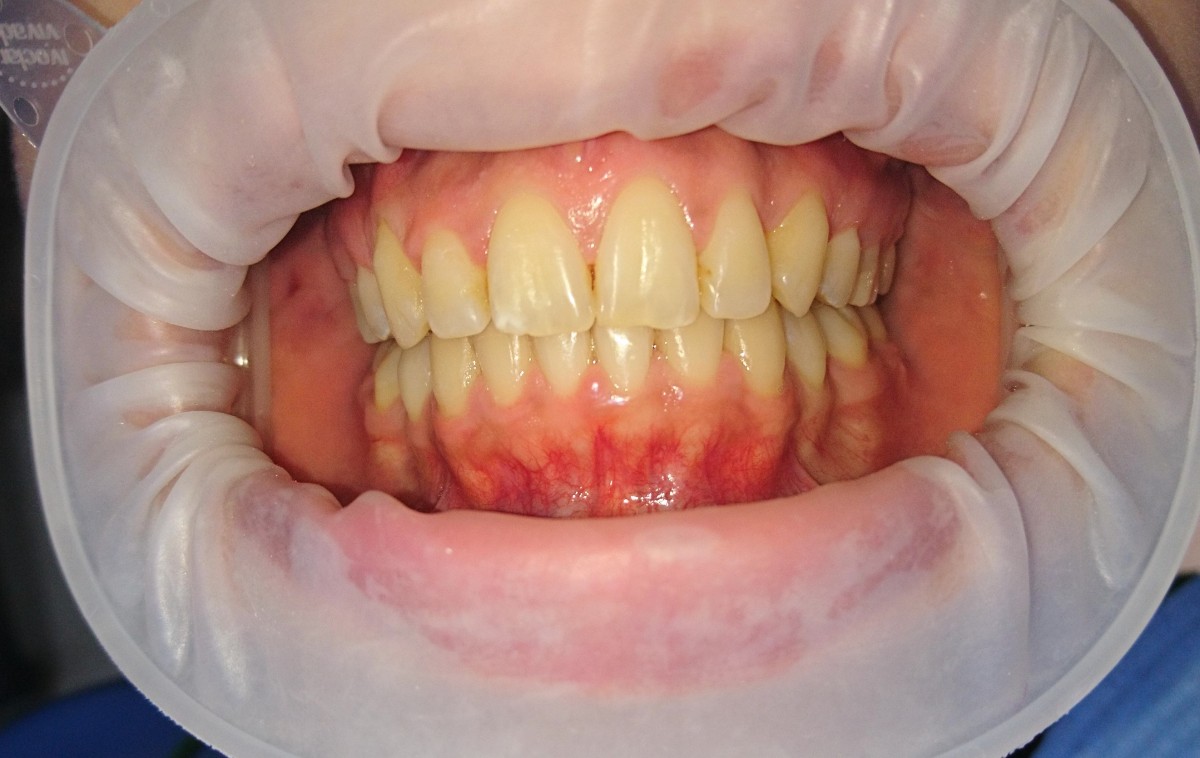

Pacient 23 ani. Extracție 1.4, 2.4, 3.5, 4.5, aparat ortodontic fix ceramic.